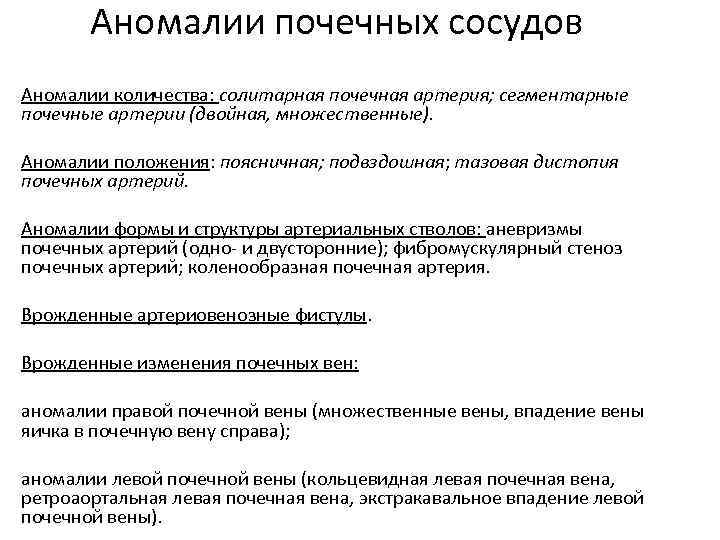

Аномалии почечных сосудов Аномалии количества: солитарная почечная артерия; сегментарные почечные артерии (двойная, множественные). Аномалии положения: поясничная; подвздошная; тазовая дистопия почечных артерий. Аномалии формы и структуры артериальных стволов: аневризмы почечных артерий (одно- и двусторонние); фибромускулярный стеноз почечных артерий; коленообразная почечная артерия. Врожденные артериовенозные фистулы. Врожденные изменения почечных вен: аномалии правой почечной вены (множественные вены, впадение вены яичка в почечную вену справа); аномалии левой почечной вены (кольцевидная левая почечная вена, ретроаортальная левая почечная вена, экстракавальное впадение левой почечной вены).

Аномалии почечных сосудов Аномалии количества: солитарная почечная артерия; сегментарные почечные артерии (двойная, множественные). Аномалии положения: поясничная; подвздошная; тазовая дистопия почечных артерий. Аномалии формы и структуры артериальных стволов: аневризмы почечных артерий (одно- и двусторонние); фибромускулярный стеноз почечных артерий; коленообразная почечная артерия. Врожденные артериовенозные фистулы. Врожденные изменения почечных вен: аномалии правой почечной вены (множественные вены, впадение вены яичка в почечную вену справа); аномалии левой почечной вены (кольцевидная левая почечная вена, ретроаортальная левая почечная вена, экстракавальное впадение левой почечной вены).

Аневризмы почечной артерии

Аневризмы почечной артерии